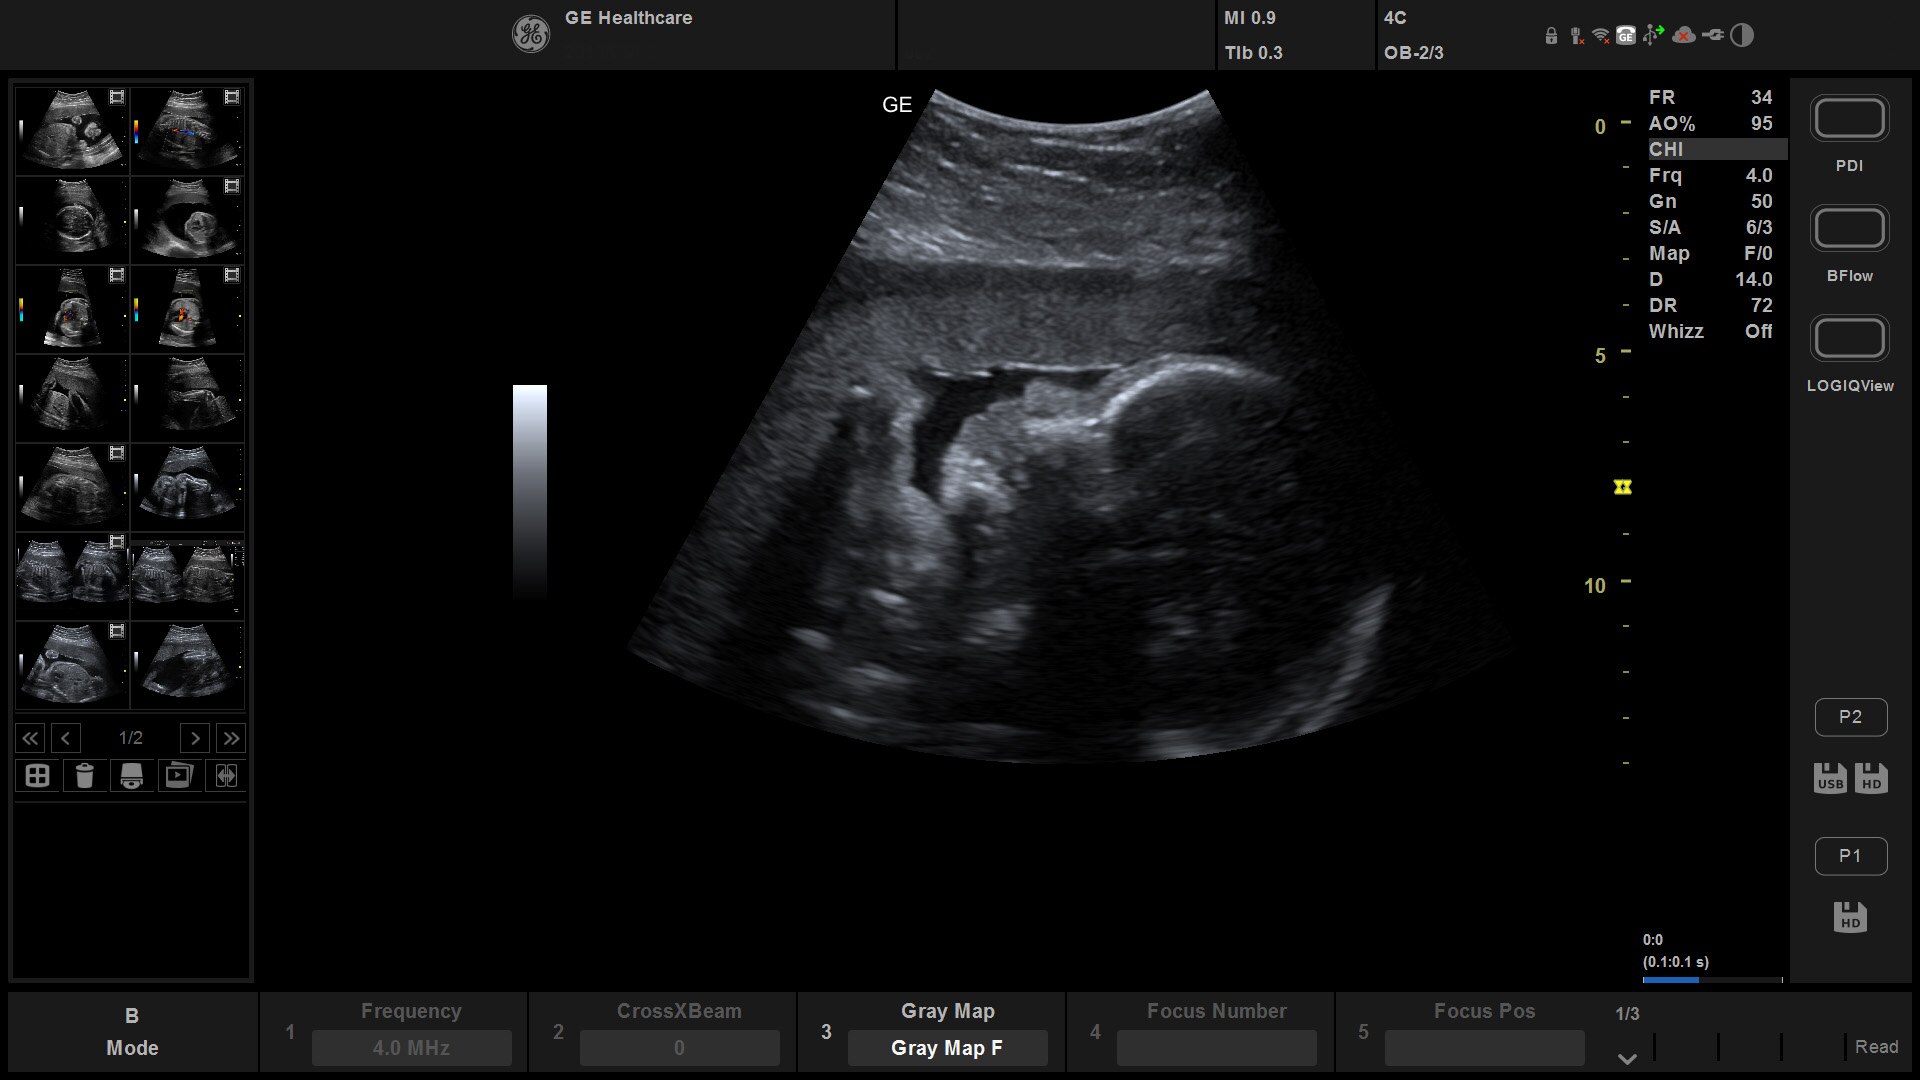

Suited for abdominal, small parts, cardiac, OB/GYN, vascular, and MSK exams

Versana Active delivers the imaging capability of a console in a hand-carried, lightweight package that enables you to actively take your system to your patients, on premises, or remote facilities. The reliable system brings the agility of a laptop unit with the capability for attaching to a cart. Adaptable to cover a broad range of everyday exams, it is easy to carry to clinics, offices, and beyond.

Versana Active features a wide range of advanced clinical applications and automated tools that simplify exams, streamline workflow, and enable fast, high-volume scanning to help you diagnose a wide spectrum of patient conditions.

4D¹

Aids decision making by enabling additional dimensions in real time